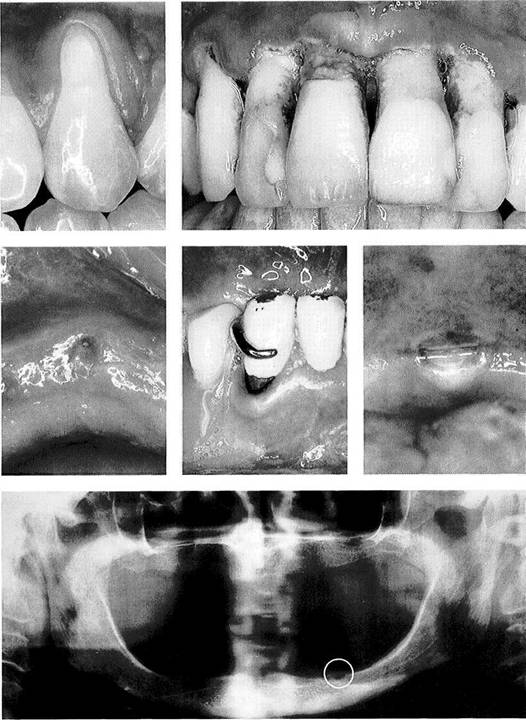

Dentition of a 35-year-old patient exhibiting severe damage from caries and periodontal disease. There is diffuse radiating pain in the right half of the face.

Acute necrotizing gingivitis (peri­odontitis) in a patient with full­blown AIDS.

Left: Pronounced localized gingival recession with severe hypersensi­tivity at the neck of the tooth.

Traumatic mucosal defects

Left: The same region as shown in the center photograph. The mucos­al defect caused a neuralgia-like pain radiating to the right eye.

Center: The mucosal lesion was caused by occlusion of the oppos­ing tooth against the alveolar ridge.

Right: Iatrogenic ulcer in the mid­line at the transition from hard to soft palate as the result of a posteri­orly overextended denture border.

Radiographic findings

This panoramic radiograph shows extensive atrophy of the edentu­lous mandible with exposure of the left mental foramen (circled). Me­chanical irritation of the mental nerve by the lower denture caused pain encompassing the left tem­poromandibular joint region.